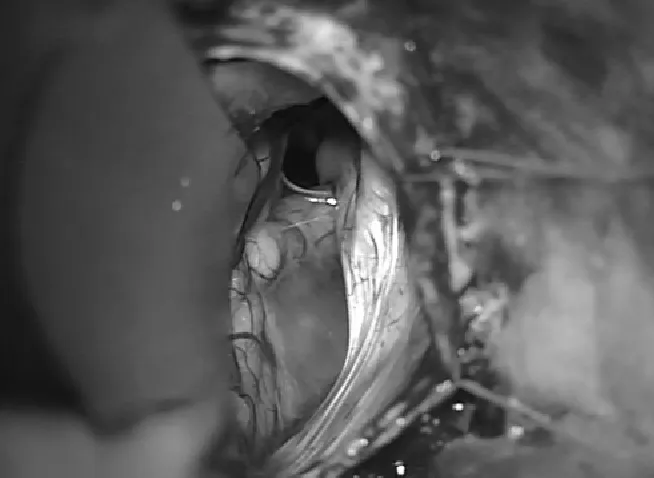

对于这类患者,手术并非简单的囊肿剔除,而是需要在保护重要神经结构和彻底缓解症状之间找到平衡点。Di Rocco教授团队采用的手术策略包括:首先,通过术中神经电生理监测实时评估第七、八对脑神经的功能状态,这使得医生能够在操作过程中随时调整策略,避免进一步伤害。其次,选择恰当的手术入路——通过影像学数据精确定位囊肿与周围神经血管的关系,制定个体化的手术方案。第三,术后的影像学复查(MRI对比)显示,虽然囊肿被成功切除或部分引流,但患者的神经结构和脊液通道得到了明显改善。